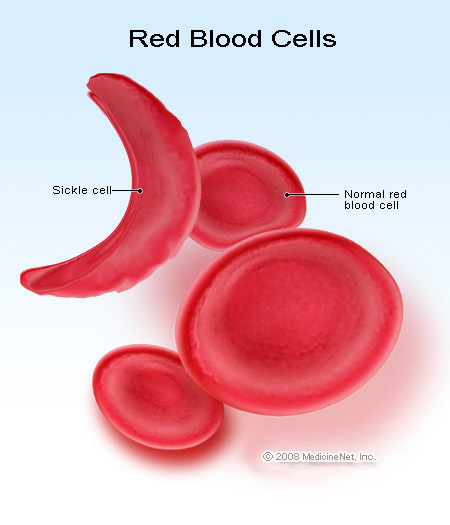

- Blood defects and diseases (e.g. leukemia, sickle cell anaemia etc.)